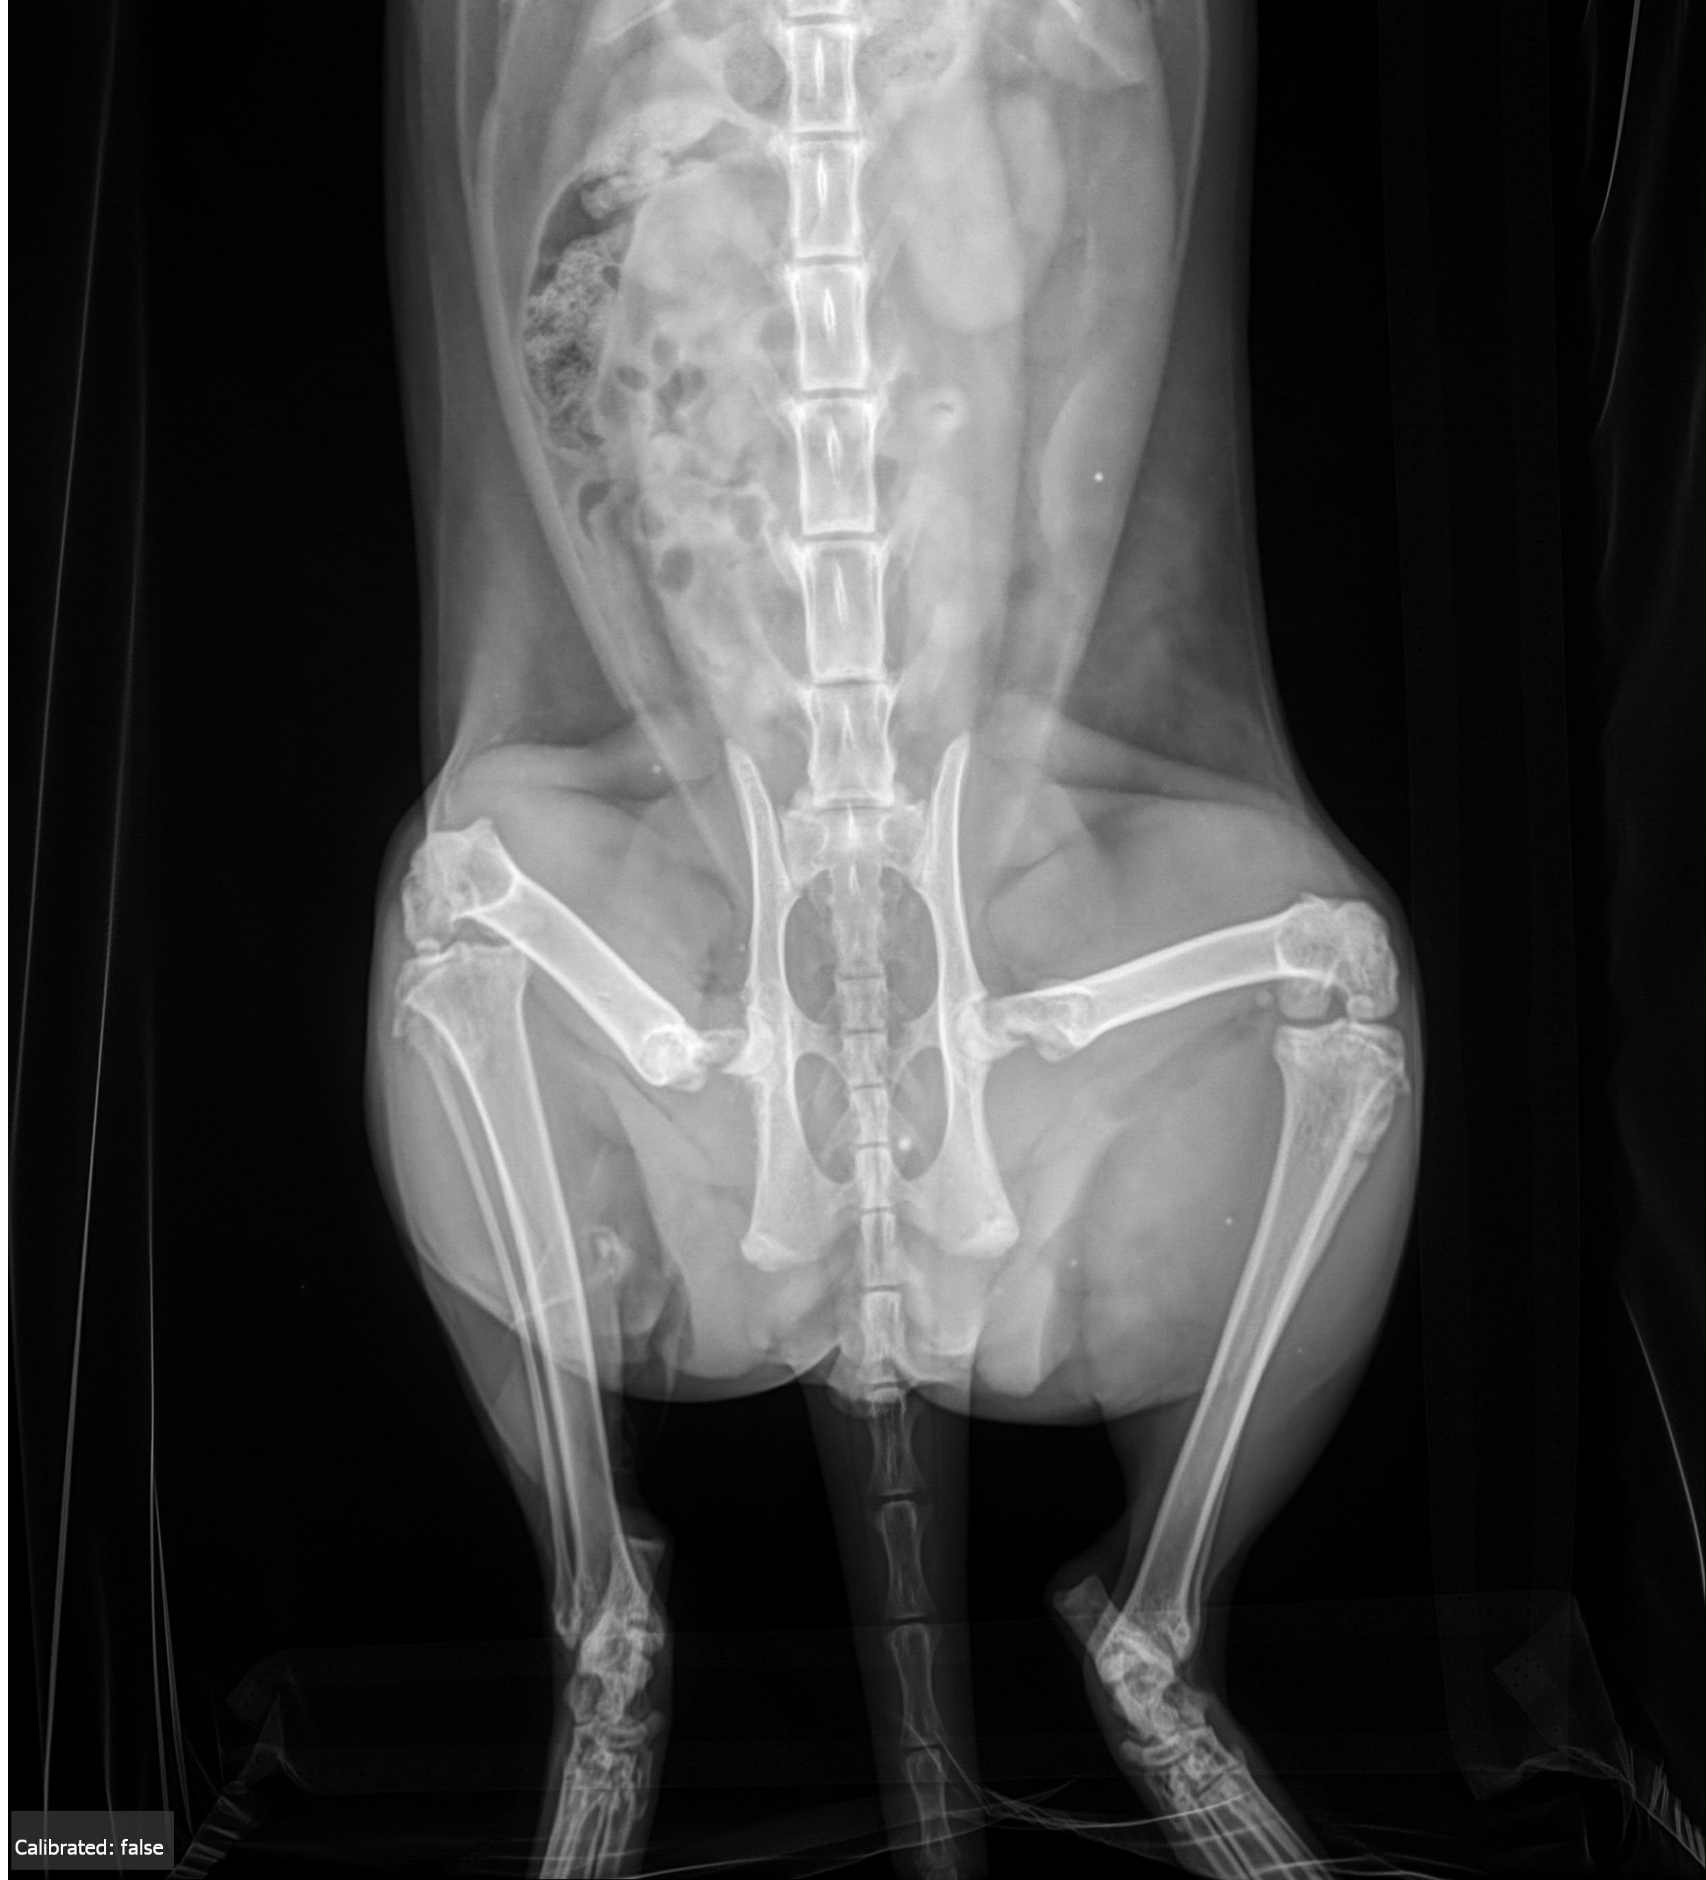

Sweet Waffles is in desperate need of our help. This gentle, loving cat recently suffered a devastating accident that left him with both of his femurs broken. He is in pain and cannot walk without immediate surgical intervention. Without surgery, his future is heartbreakingly uncertain.